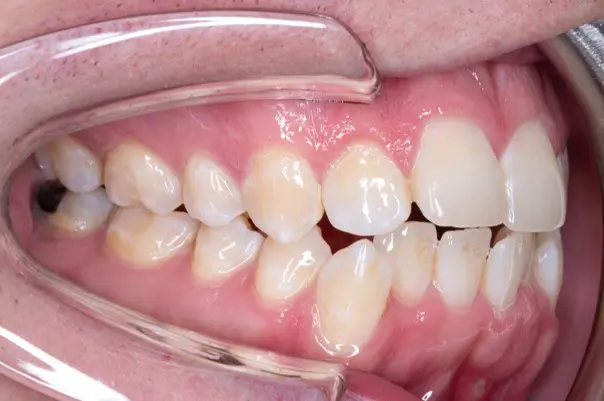

Crossbite/Uneven Bite

Before

After